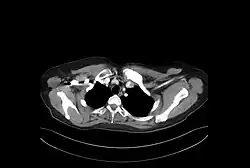

Esta síndrome possui etiologia desconhecida. É caracterizada por:

• 1)Sinovite - Inflamação da cápsula sinovial

• 4)Hiperostose - Espessamento irregular do tecido ósseo subperiosteal

• 5)Osteíte inflamatória